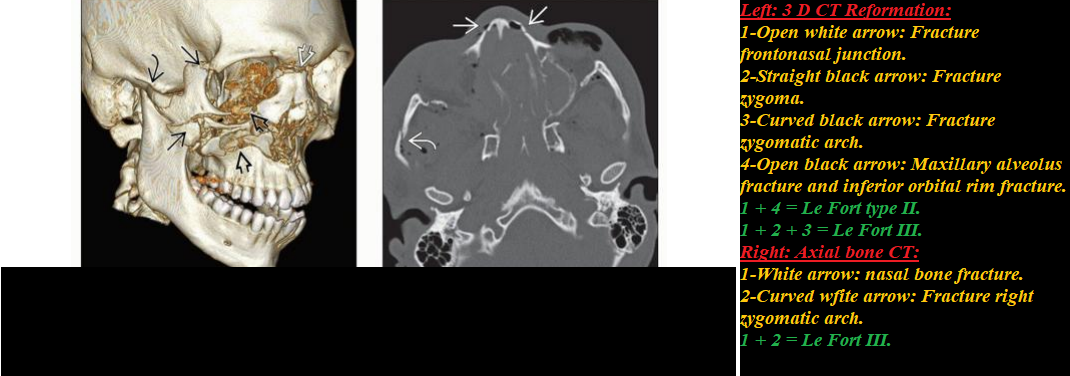

Head & Neck Emergency:Diagnostic Imaging (Click on image to magnify). Get link Facebook X Pinterest Email Other Apps - February 08, 2020 Get link Facebook X Pinterest Email Other Apps Comments